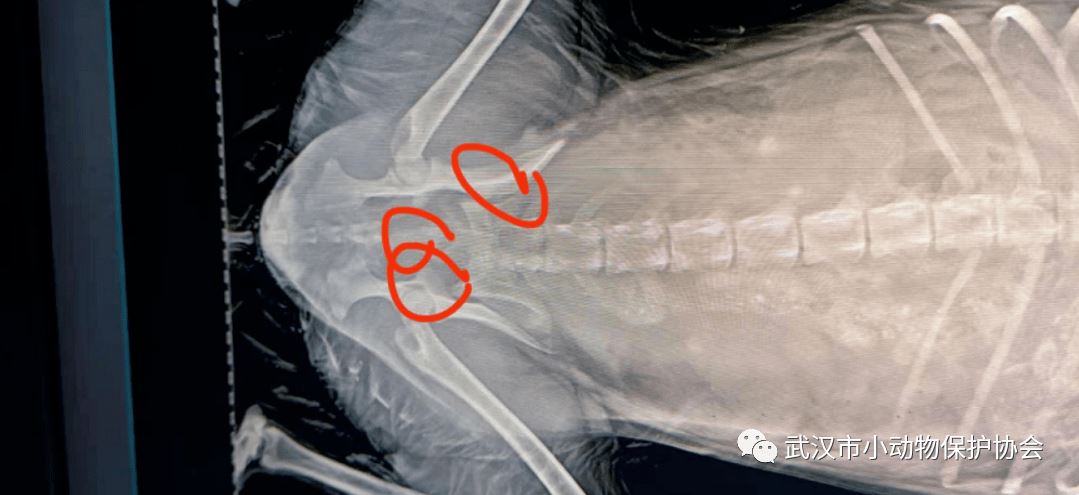

救助经过:网友电话联系协会,在金银潭地铁站停车场旁有一只流浪狗趟在地上,屁股有鲜血,随后前往现场救助,已经送样唯医宠物医院检查。狗狗要腰椎,尾椎和骨盆有多达9处的骨折,后腿没有神经疼痛反射,外阴撕裂,膀胱破损。综合考虑后,选择了为它安乐。

动物信息:京巴串,性别,母,年纪,六岁左右,姓名,梅超风

狗狗的检查和处置费用是1000元。